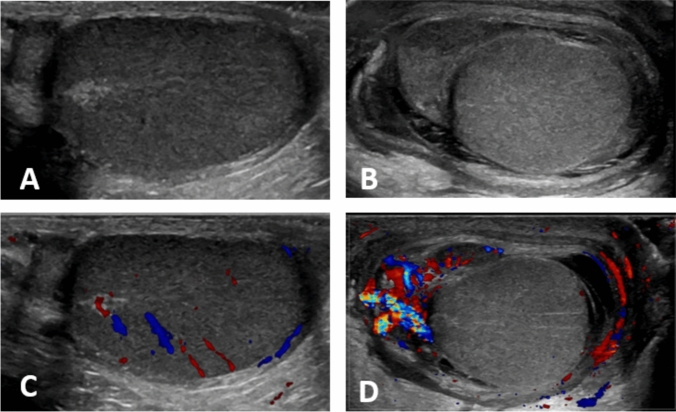

Results: A total of 142 patients with a median age of 9 years were reviewed. Of these, 137 cases had favorable testicular outcomes, while five cases had poor outcomes, including three cases of testicular or epidydimal atrophy, one case of testicular necrosis, and one case of testicular necrosis and abscess. Fever (p = 0.001), C-reactive protein (CRP) levels (p = 0.002), and decreased testicular blood flow on ultrasonography (p < 0.001) were significantly associated with poor testicular outcomes.

Conclusion: Fever, CRP levels, and decreased testicular blood flow are risk factors for unfavorable testicular outcomes in pediatric patients with AE. Patients with these risk factors require careful monitoring and may benefit from aggressive management strategies.